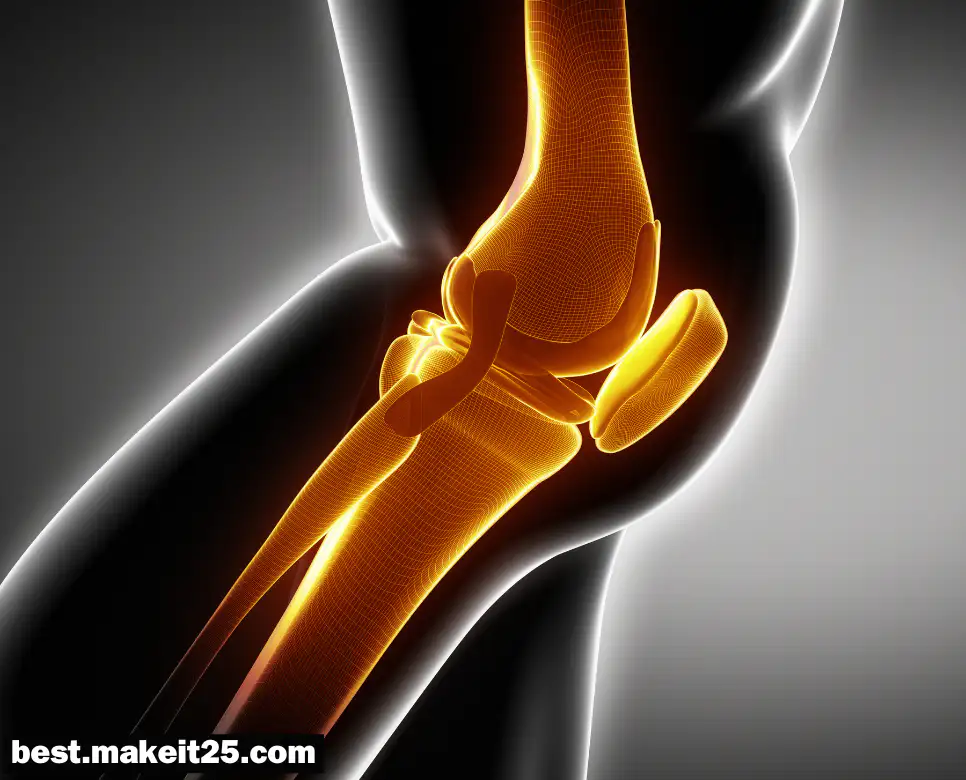

LMC

LMC는 의학 용어로, Lateral Meniscal Cyst 또는 Lateral Meniscus의 약어로 사용될 수 있습니다. 한국어로는 외측 반월상 연골판 또는 외측 반월상 연골 낭종을 의미합니다. 이는 무릎 관절의 중요한 구조물인 반월상 연골판과 관련된 용어로, 무릎의 안정성과 움직임을 조절하는 데 중요한 역할을 합니다.

LMC (Lateral Meniscal Cyst)

외측 반월상 연골 낭종은 연골 내부 또는 주변에 액체가 차서 형성된 낭종을 말합니다. 이러한 낭종은 다음과 같은 증상을 동반할 수 있습니다:

- 무릎의 통증

- 부종

- 무릎의 움직임 제한

진단은 MRI나 초음파를 통해 이루어지며, 치료는 낭종의 크기와 증상에 따라 비수술적 방법이나 수술적 방법이 고려될 수 있습니다.

LMC (Lateral Meniscus)

외측 반월상 연골판은 무릎 관절의 외측에 위치하며, 체중 전달, 외력의 분산, 관절 연골 보호, 관절의 안정성 및 윤활 기능 등을 담당합니다. 반월상 연골판의 손상은 다음과 같은 상황에서 발생할 수 있습니다:

- 운동 중 부상

- 나이가 들어감에 따른 퇴행성 변화

치료는 파열의 정도와 증상에 따라 약물 치료, 물리 치료, 관절 주사, 또는 수술적 절제가 필요할 수 있습니다.

LMC는 무릎의 건강과 기능을 유지하는 데 중요한 역할을 합니다. 의료진은 LMC 관련 질환을 진단하고 치료함으로써 환자의 무릎 건강을 회복하고, 환자는 적절한 치료를 통해 일상생활로의 복귀를 기대할 수 있습니다.